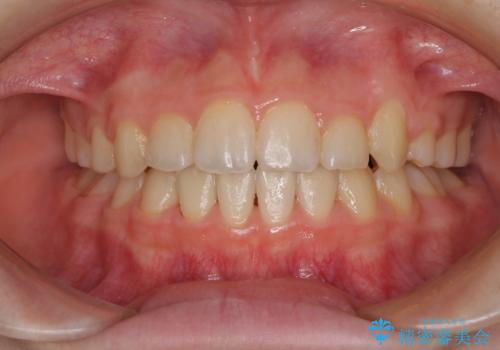

乳歯が残っている 目立たない装置での抜歯矯正

- 八重歯と乳歯が残っていることを気にして来院された患者様です。

乳歯が3歯残っており、下顎は左右ともに後続永久歯がない状態でした。

口元が突出しており、口が閉じにくかったため、乳歯を含め上下5歯を抜歯して矯正治療を行うこととしました。

下顎の乳歯は永久歯と比べて幅が大きいため、抜歯した場合のスペースが大きく、治療には長期間を要することが一般的です。

今回の患者様は中学生ということもあり、成人の患者様と比べ動きが速く、2年間で治療を終えることができました。